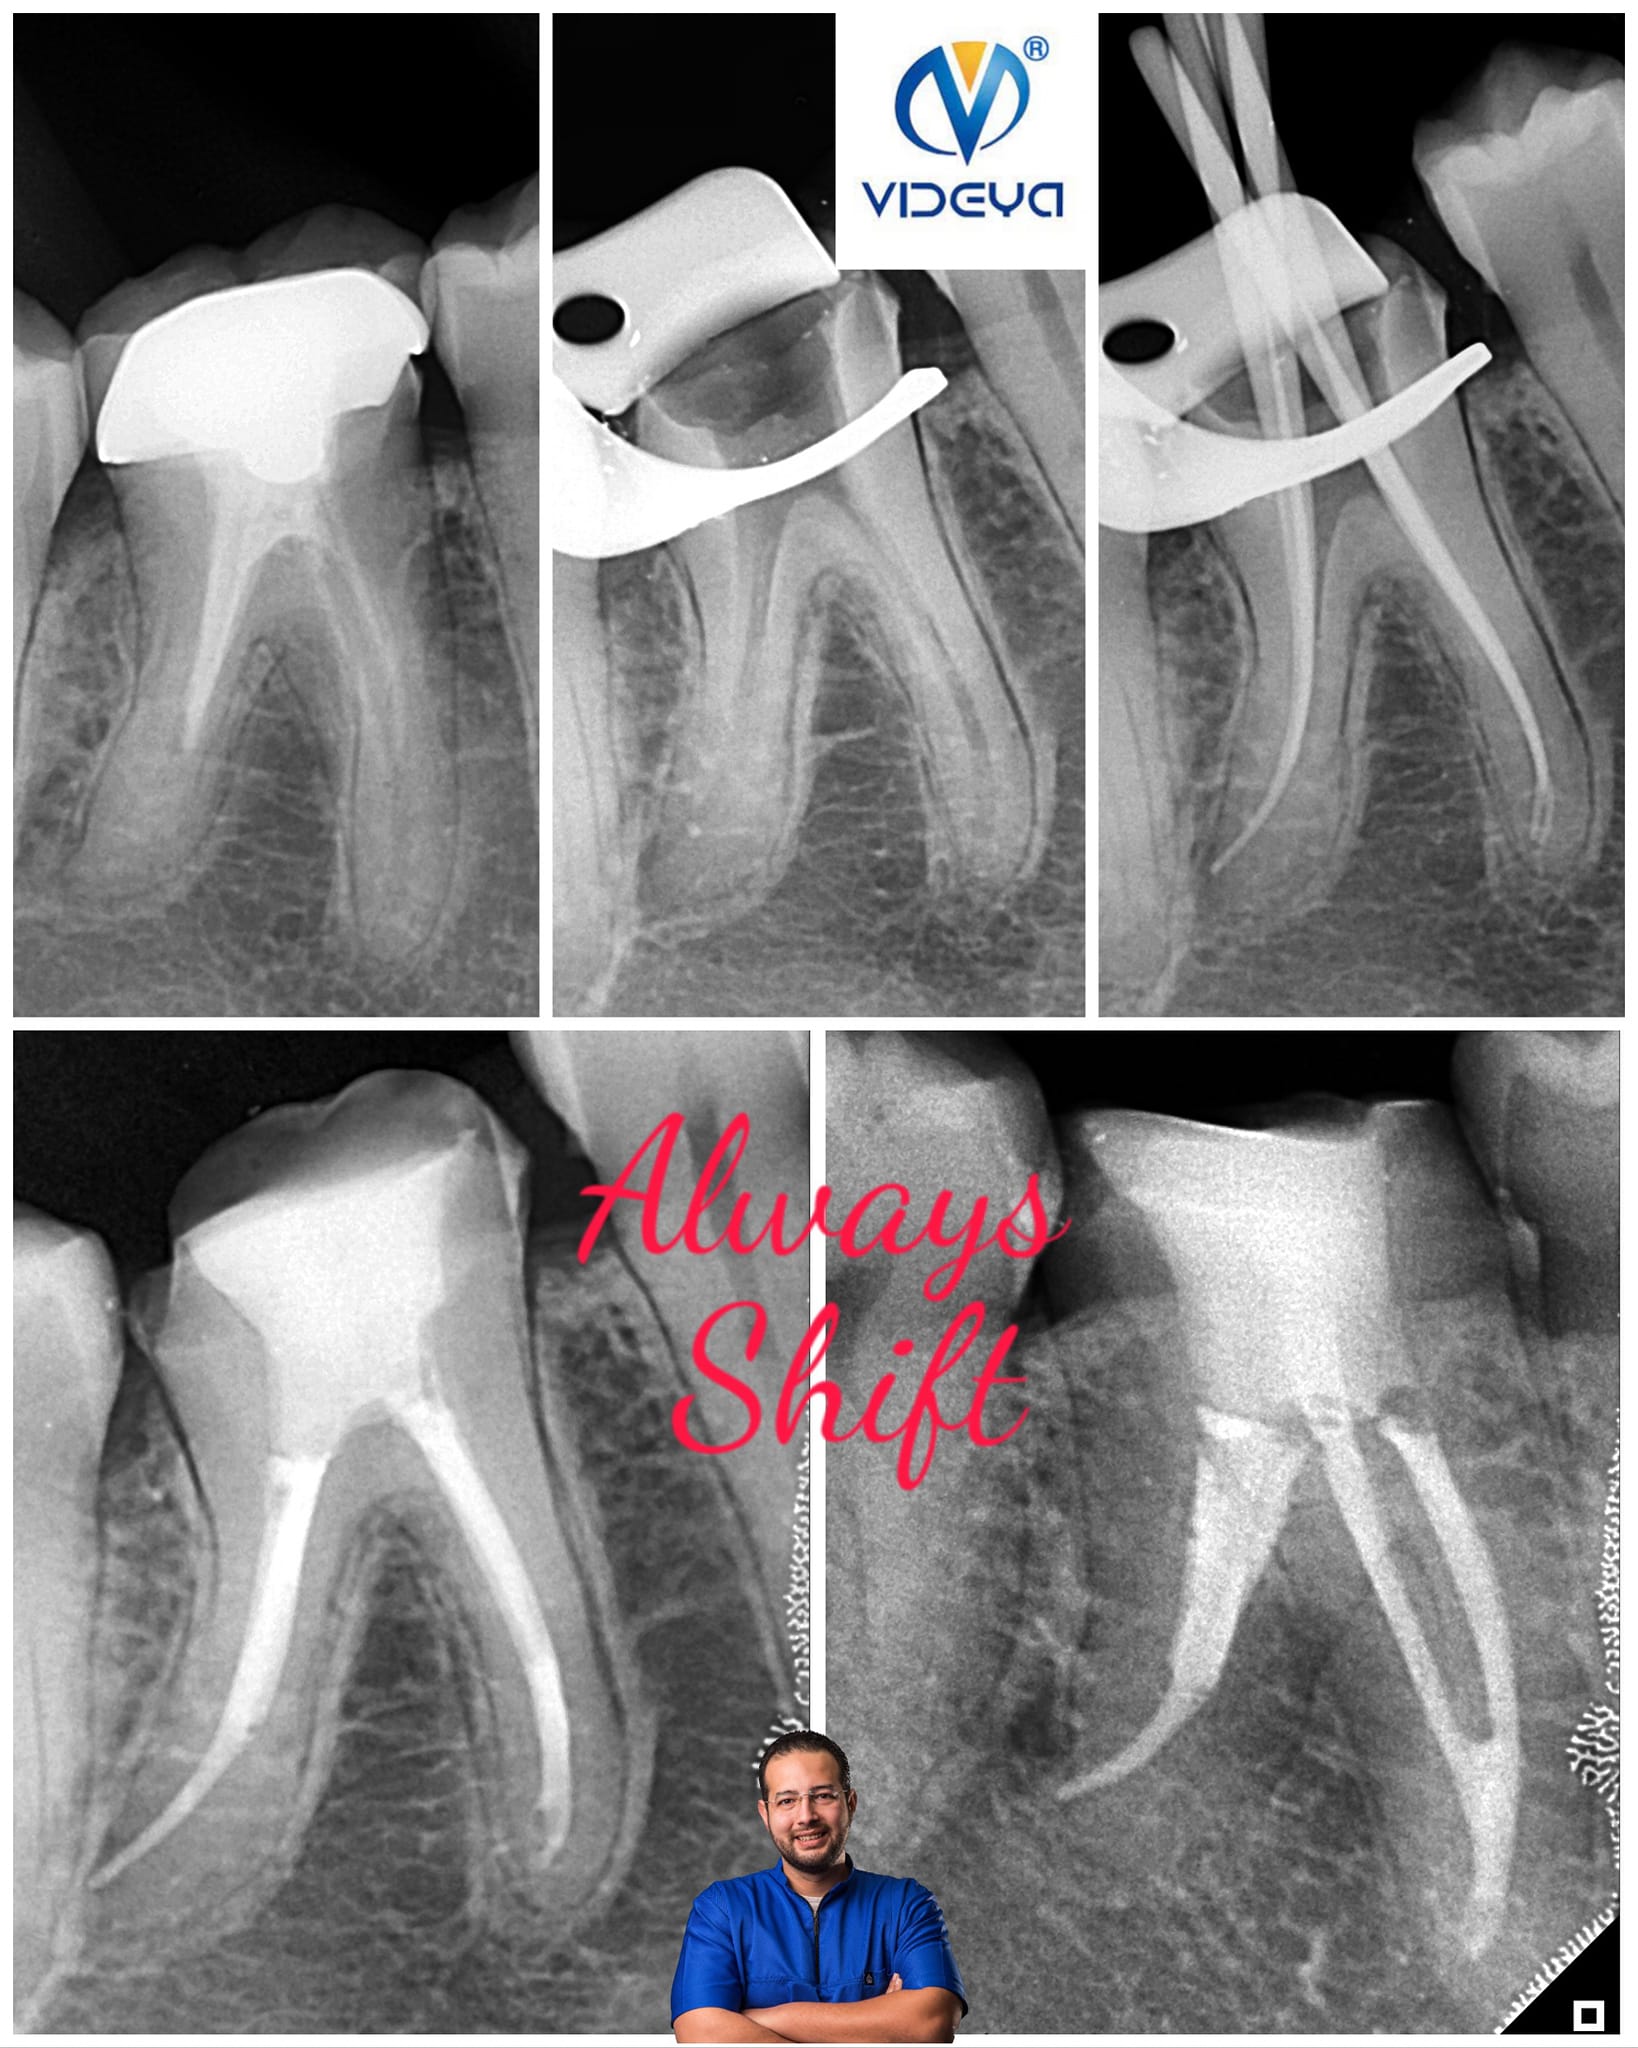

Curvy With Videya Dental Blue Files